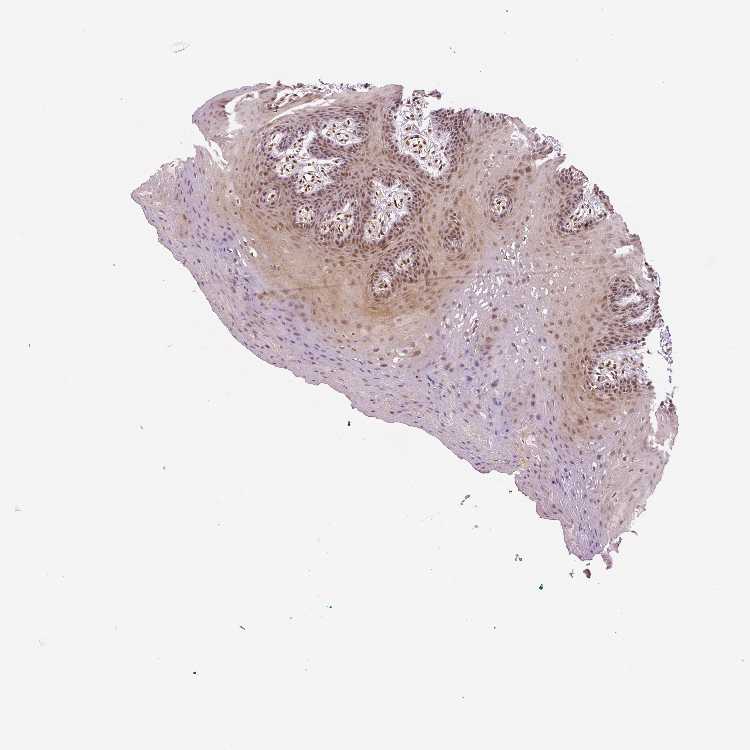

TISSUE PRIMARY DATA ORAL MUCOSA Show tissue menu

Oral mucosa

ORAL MUCOSA - Antibody stainingi

Antibody staining in the annotated cell types in the current human tissue is reported as not detected, low, medium, or high, based on conventional immunohistochemistry profiling in selected tissues. This score is based on the combination of the staining intensity and fraction of stained cells.

Each image is clickable and will lead to virtual microscopy that enables deeper exploration of all samples and also displays staining intensity scores, fraction scores and subcellular localization as well as patient and tissue information for each sample.

Antibody HPA001671Antibody HPA058603Antibody CAB003859Antibody CAB068241Antibody CAB068242

Squamous epithelial cells HighMediumMediumLowMedium